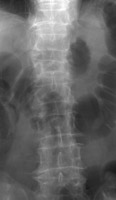

Compression fractures of the spine are common in elderly and osteoporotic patients. They result from anterior or lateral flexion. The typical appearance is loss of height of the anterior aspect of the vertebral body with preservation of the posterior elements and generally the posterior aspect of the vertebral body. On the frontal view, there may be subtle deviation of the paraspinous line due to edema. Differentiation from a pathologic fracture of the spine due to a metastasis is usually of clinical concern, but simple compression fractures are usually due to osteoporosis.

- Click on the image for a larger versionDLateral radiograph of the lumbar spine. Two years prior there was osteopenia, but the fracture was not present.